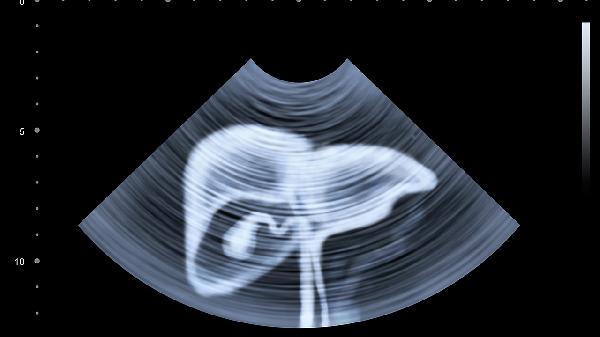

二、肝脏发出的缺水警报

1.眼球干涩发黄

当肝细胞储水能力下降时,眼周黏膜会率先出现干燥信号。持续缺水可能导致胆红素代谢异常,让眼白泛出隐隐黄色。